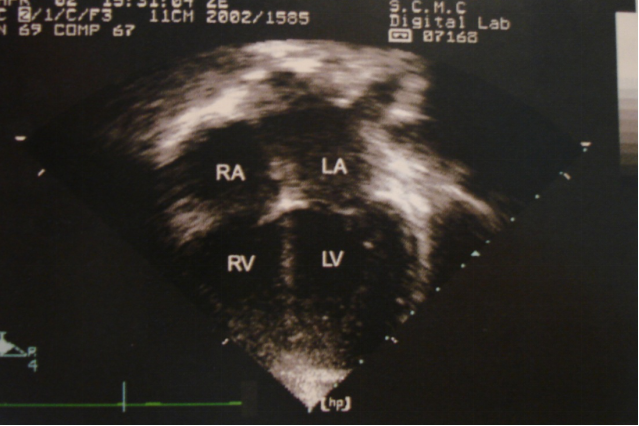

二维超声心动图

胸骨旁长轴切面 四腔心切面